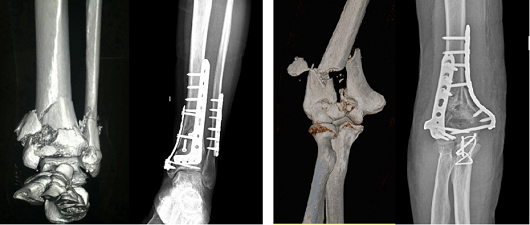

二、四肢骨折

脛腓骨遠(yuǎn)端粉碎性骨折治療前、后 肘關(guān)節(jié)肱骨遠(yuǎn)端粉碎性骨折治療前、后